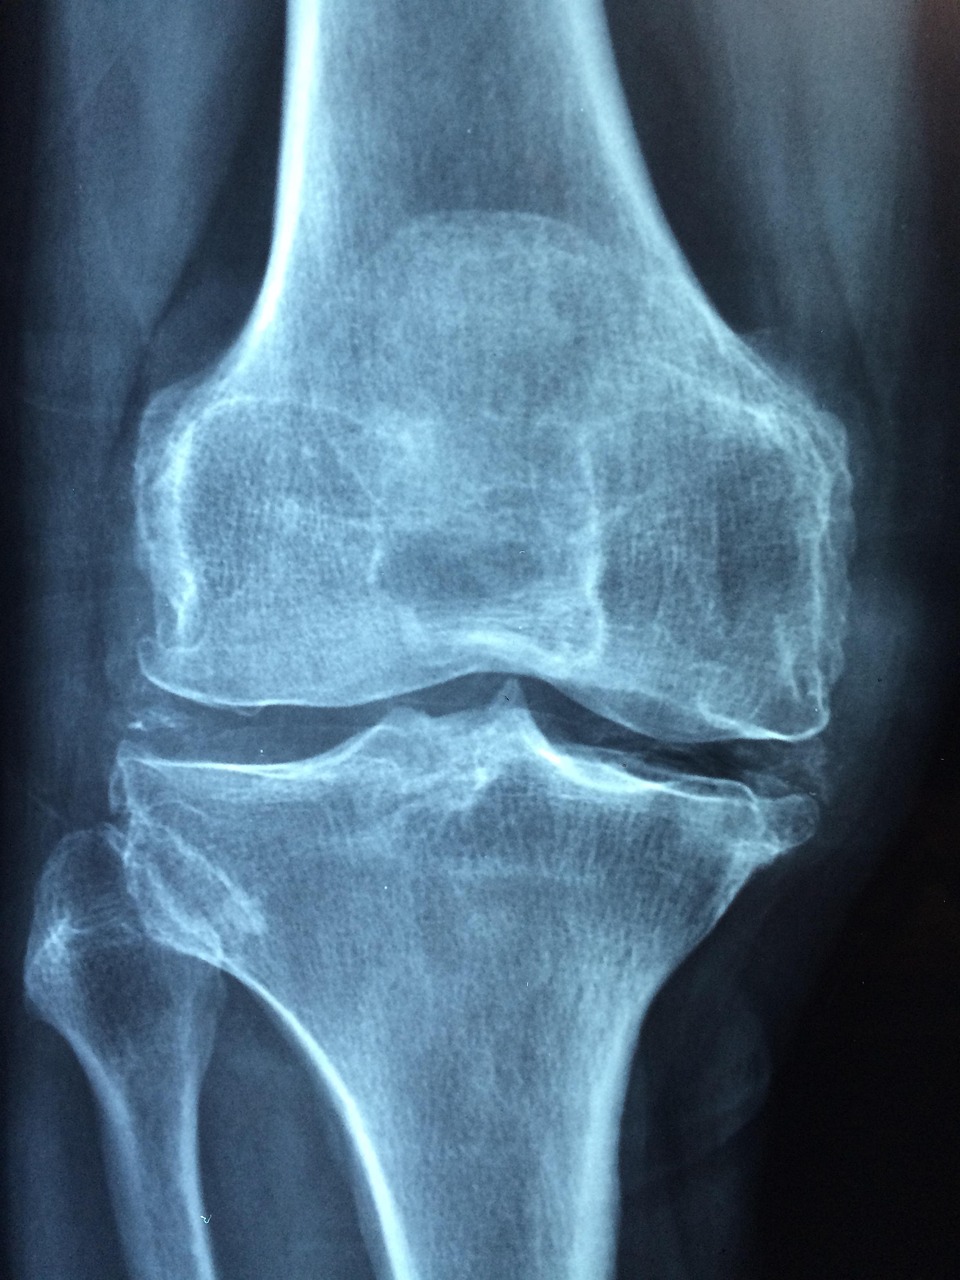

나이가 들면서 몸이 약해졌다고 느끼는 이들이 많다. 그러나 단순한 체력 저하가 아닌, 뼈의 내부 구조가 약해지고 밀도가 낮아지는 변화가 원인일 수 있다. 특히 고령자에서 가장 흔히 나타나는 근골격계 질환 중 하나는 골다공증이다. 뼈가 점점 비어가고 약해지면서 외부 충격에 매우 취약해지며, 낙상 시 쉽게 골절로 이어질 수 있다. 이로 인해 병원 입원, 수술, 장기간의 회복과 운동 장애로 이어지는 사례가 많으며, 일부는 일상으로의 복귀가 어려울 정도로 기능을 잃기도 한다.

골다공증은 오랜 기간 서서히 진행되기 때문에 초기에는 자각 증상이 거의 없다. 허리가 구부정해지거나, 예전보다 키가 줄어든 것 같은 느낌이 들 때, 혹은 별다른 이유 없이 요통이 계속될 때에는 이미 상당한 수준으로 진행된 경우가 많다. 특히 여성은 폐경 이후 에스트로겐 분비가 급격히 감소하면서 골 손실 속도가 빨라진다. 따라서 증상이 나타나기 전, 예방을 중심으로 한 관리가 매우 중요하다.

골다공증 검사는 1~2년에 한 번 정도는 정기적으로 받아야 한다. 특히 65세 이상 여성, 70세 이상 남성은 별다른 증상이 없더라도 골밀도 검사를 통해 현재 상태를 확인하고, 필요한 경우 약물치료나 보충제를 활용한 적극적인 관리를 시작하는 것이 좋다. 또한 골절을 예방하기 위해 가정 내 환경도 점검할 필요가 있다. 미끄러운 욕실 바닥, 낮은 조명, 걸려 넘어질 수 있는 전선이나 카펫 등은 모두 낙상의 원인이 될 수 있다. 실내 안전 손잡이 설치, 조명 개선, 미끄럼 방지 패드 활용 등 간단한 환경 조성만으로도 사고를 크게 줄일 수 있다.